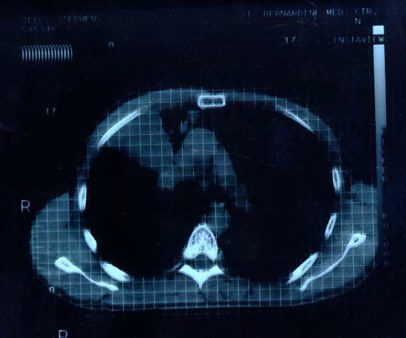

Scan 15th March 1999 No3